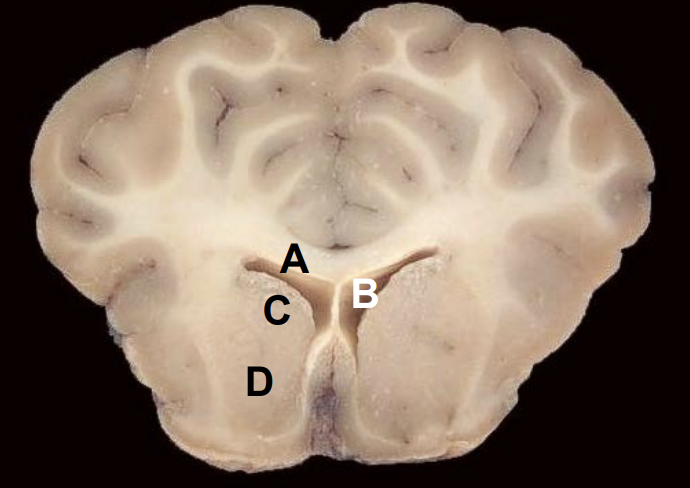

Q

A

Lateral ventricle

3

Caudate nucleus

4

Putamen